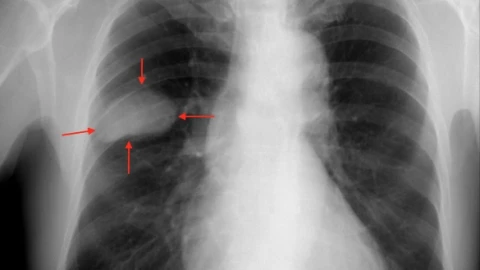

El desarrollo de la aplicación estuvo a cargo de la empresa Qure.Al y es capaz de ubicar con facilidad los nódulos pulmonares solitarios, que suelen medir menos de tres centímetros, mismos que generalmente se encuentran por accidente al realizar radiografías o tomografías computarizadas, según explican especialistas en salud.

Los nódulos pulmonares son indicadores tempranos de cáncer de pulmón, enfermedad que durante 2020 registró siete mil 811 casos nuevos y seis mil 733 muertes en México, según datos del Instituto Nacional de Salud Pública.